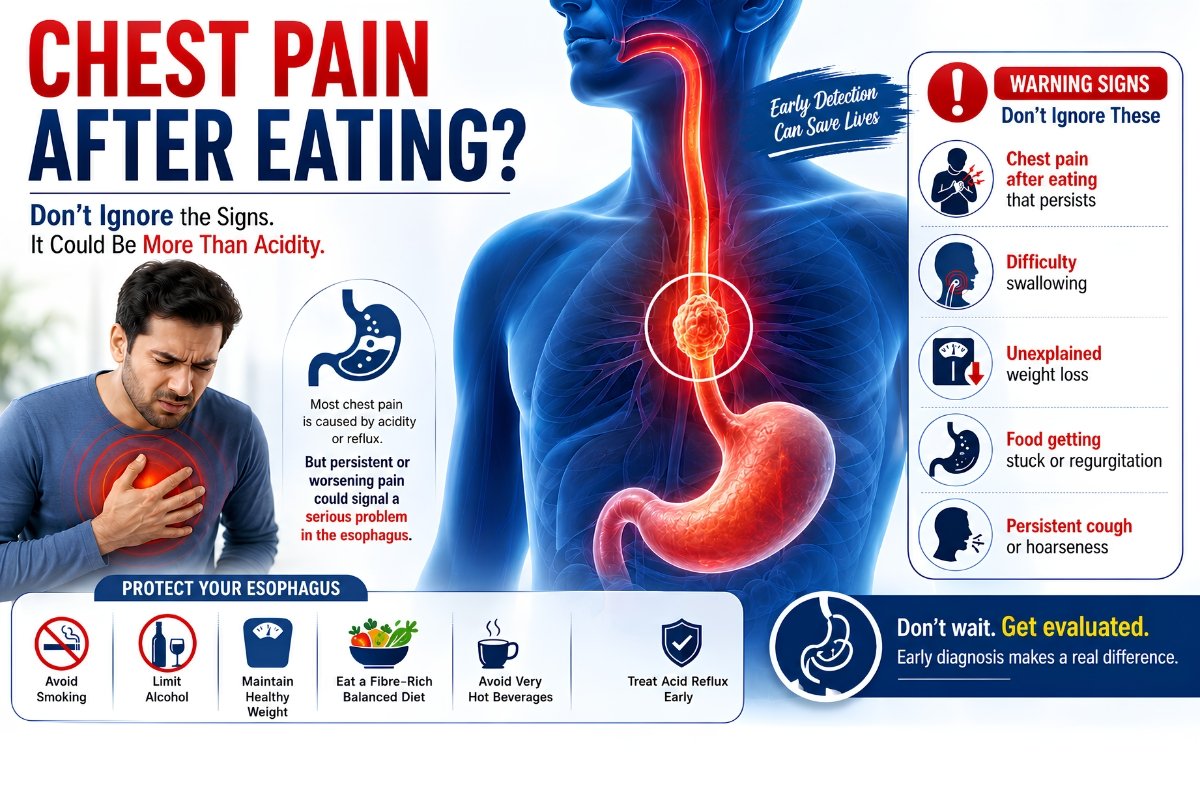

Is Chest Pain After Eating a Warning Sign of Esophageal Cancer?